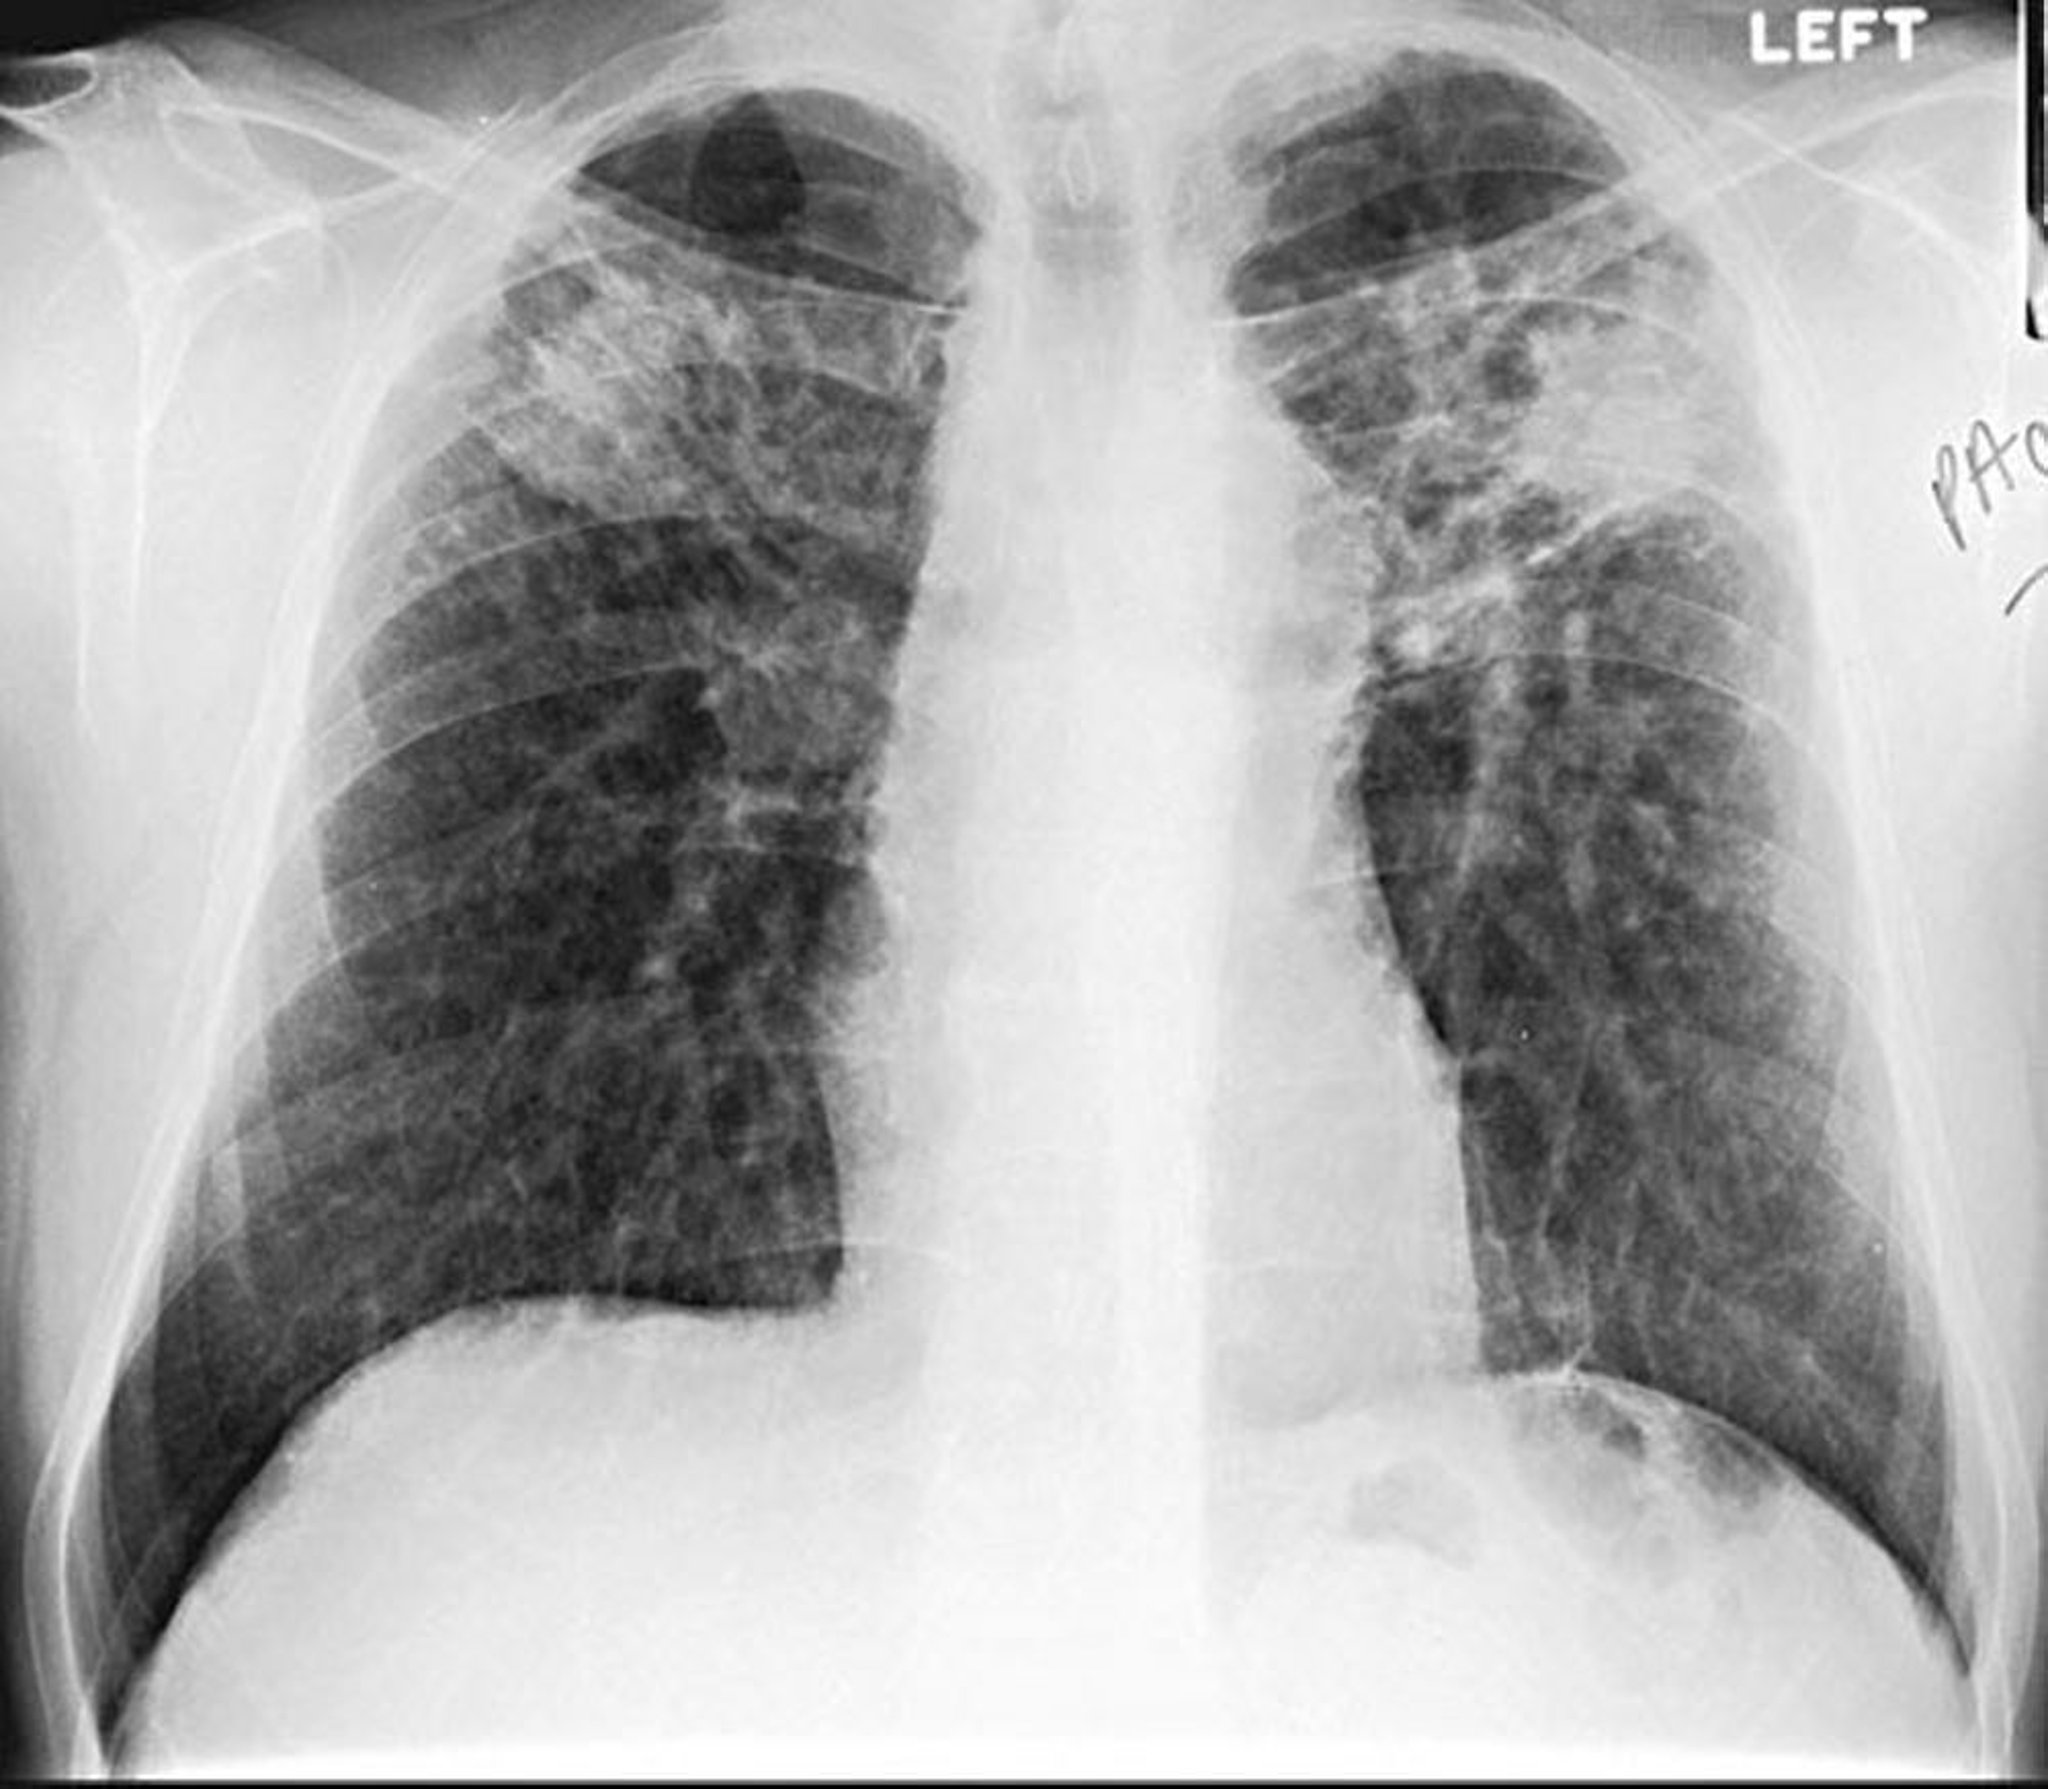

Silicose, conglomérat

Image courtoisie de David W. Cugell, MD.